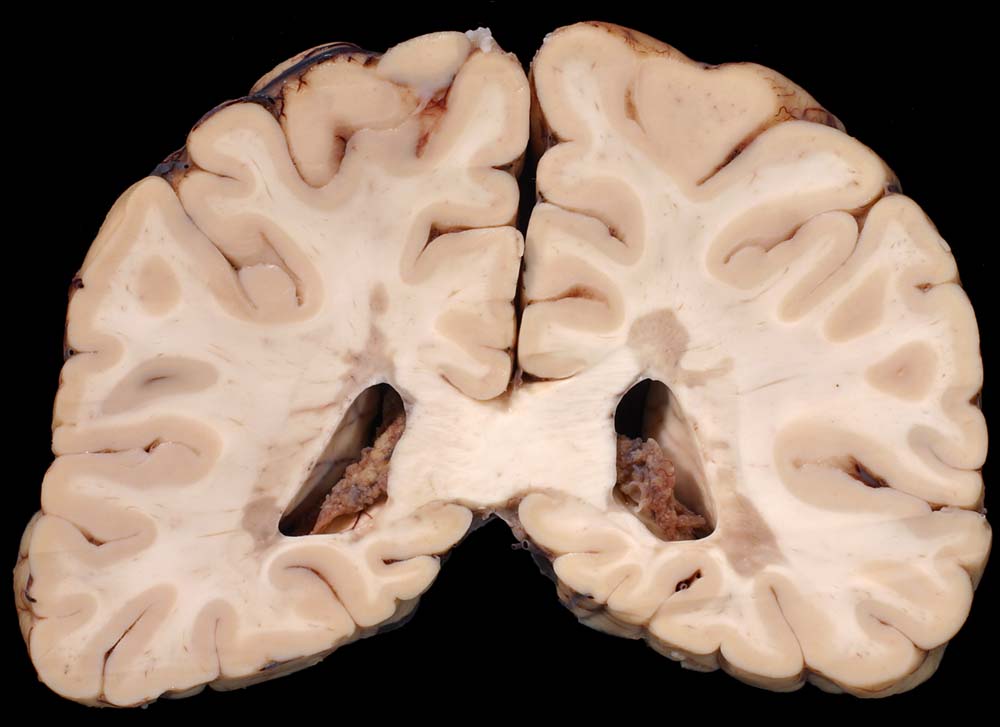

PathoPic ID 8792 - Periventrikulär betonte Entmarkungsherde bei multipler Sklerose

Periventrikulär betonte Entmarkungsherde bei multipler Sklerose

Periventrikuläre irregulär begrenzte Grauverfärbung des Marklagers.

Multiple Sklerose (Erstdiagnose vor 30 Jahren) mit spastischer Paraparese und neurogener Blasenmotorikstörung.